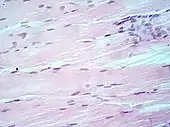

H&E stain

H&E is the combination of two histological stains: hematoxylin and eosin. The hematoxylin stains cell nuclei a purplish blue, and eosin stains the extracellular matrix and cytoplasm pink, with other structures taking on different shades, hues, and combinations of these colors.[5][6] Hence a pathologist can easily differentiate between the nuclear and cytoplasmic parts of a cell, and additionally, the overall patterns of coloration from the stain show the general layout and distribution of cells and provides a general overview of a tissue sample's structure.[7] Thus, pattern recognition, both by expert humans themselves and by software that aids those experts (in digital pathology), provides histologic information.

Hematoxylin principally colors the nuclei of cells blue or dark-purple,[6][15][14] along with a few other tissues, such as keratohyalin granules and calcified material. Eosin stains the cytoplasm and some other structures including extracellular matrix such as collagen[5][7][14] in up to five shades of pink.[8] The eosinophilic (substances that are stained by eosin)[5] structures are generally composed of intracellular or extracellular proteins. The Lewy bodies and Mallory bodies are examples of eosinophilic structures. Most of the cytoplasm is eosinophilic and is rendered pink.[10][15] Red blood cells are stained intensely red.

Muscle tissue, cell nuclei (blue-purple), cell body (pink).